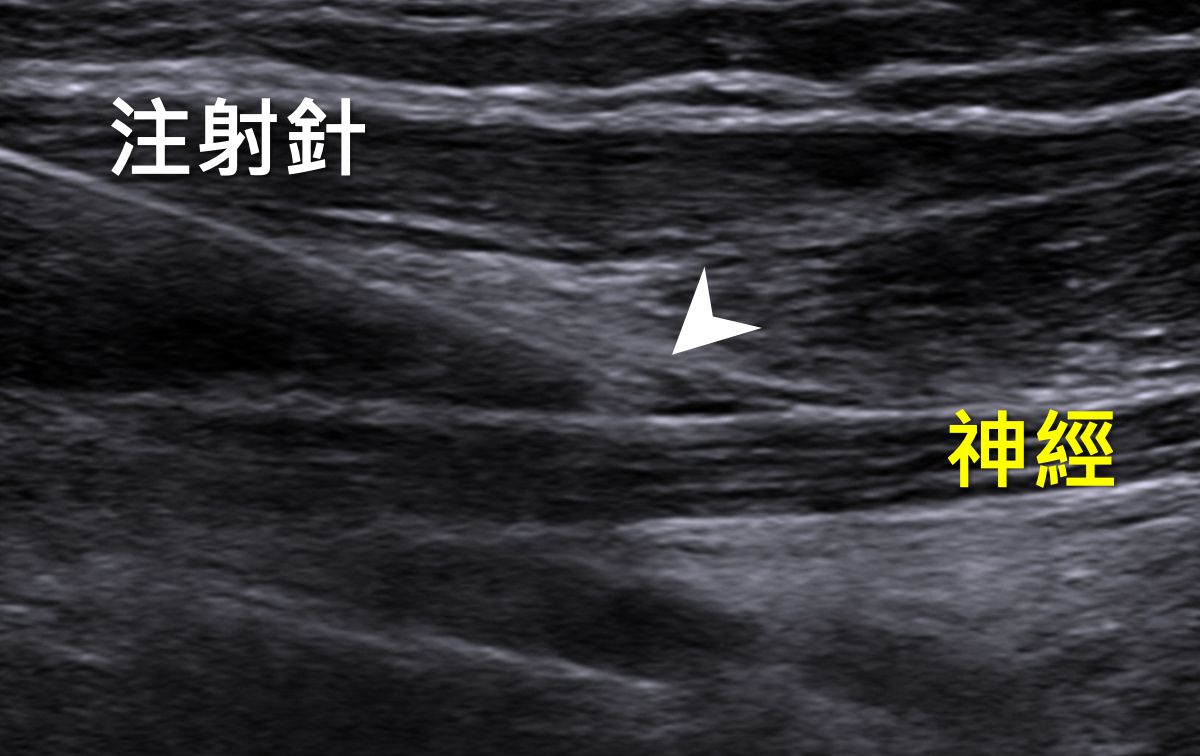

圖:利用超音波導引「神經解套注射」精準地將藥劑注射到受損神經處。

再次回診評估時,與醫師討論後,陳小姐接受了超音波導引「神經解套注射」。藉由注射葡萄糖水分離神經與鄰近組織解除神經壓迫,改善神經腫脹及發炎。陳小姐在接受兩次神經解套注射的治療後並搭配積極的復健治療,手部麻痛的症狀有了大幅的改善,且手部肌力由原先4分進步成滿分5分的狀態。整體症狀已經不再困擾日常生活了。

神經解套注射,英文名nerve hydrodissection。顧名思義乃藉由注射麻醉止痛藥、生理食鹽水、低濃度葡萄糖水或自體血小板(Platelet Rich Plasma,PRP),將神經與周圍組織、筋膜或鄰近結構分開。解除神經壓迫,改善神經的血流供應,達到穩定神經、改善神經發炎之作用。此技術由美國肌骨超音波專家Thomas B. Clark 所發明。臨床上復健科醫師會在超音波的導引下進行神經穩定解套注射,精準地將低濃度葡萄糖水等藥劑注射至神經病灶周圍,解開神經壓迫之處,使疼痛獲得改善。